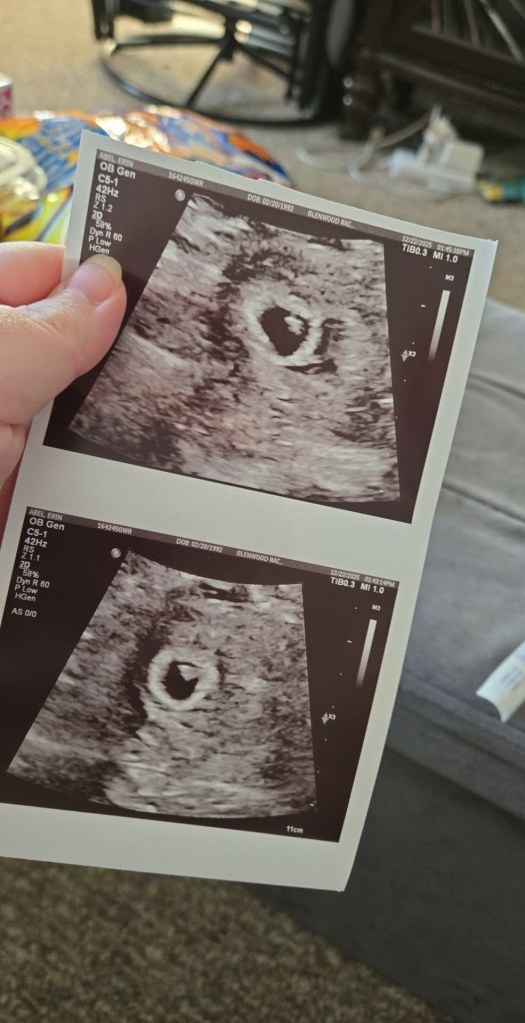

We’ve been quietly going through the process again since mid-last year, keeping our hopes high, but still appreciating that nothing about these bumpy roads is ever guaranteed.

Remarkably, Erin has birthed another surro baby since having Ernie, so we waited patiently until she and her body were ready to do this once again. Knowing that Erin is carrying for us again has made this journey feel safe, predictable and all the more exciting given when we see Erin next, not only will that mean our new arrival is imminent, but Ernie will be reunited with her nearly four years since he entered the world himself. We’ve said it before, and we’ll say it again, but there are no adequate words to express our gratitude for the extent to which Erin has changed our lives. She knows how we feel; we’re in awe of what she’s doing.